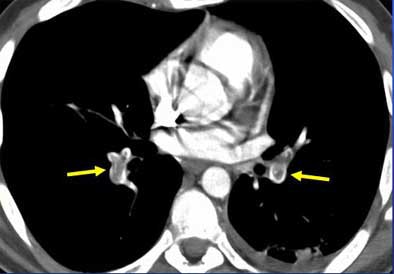

"Acute PE diagnostic findings are really quite straightforward, and are the CT equivalent of pulmonary angiographic findings," he said. "They include intraluminal filling defects and vascular cutoff -- and nothing else counts. It's important to actually see the embolus within the vessel, not just sort of say, 'Well, I think I can see it,' or 'I don't see this vessel anymore.'"

| Intraluminal filling defects reveal pulmonary embolism in target sign (above), and tram track sign (below). Images courtesy of Dr. John Mayo. |